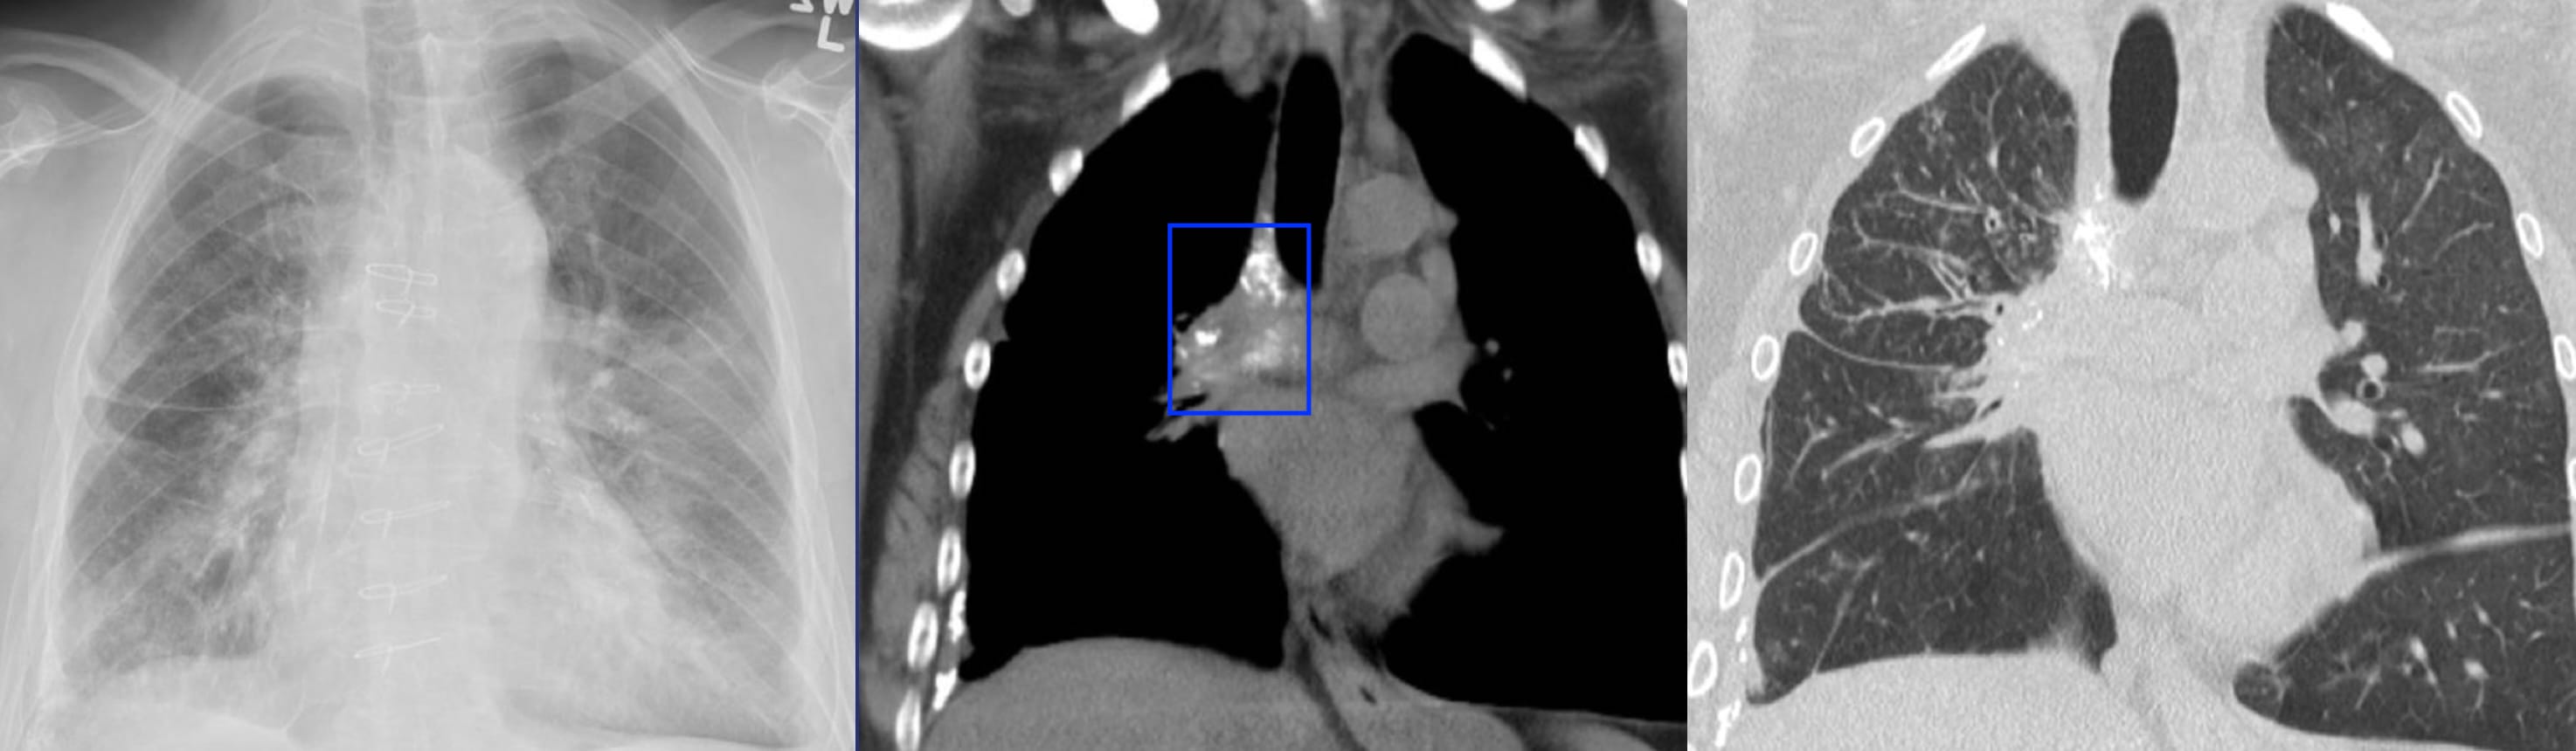

There is a history of mitral valve replacement.

A cardiac ultrasound report states: “Thrombus is present on the mechanical mitral valve prosthesis.

There is a marked pressure gradient (mean of 24mm Hg) implying thrombotic occlusion of the prosthesis.”

Diagnosis: Calcified fibrosing mediastinitis

The mediastinal tissue (blue box) encases the right superior pulmonary vein with resultant right upper lobe interstitial edema.